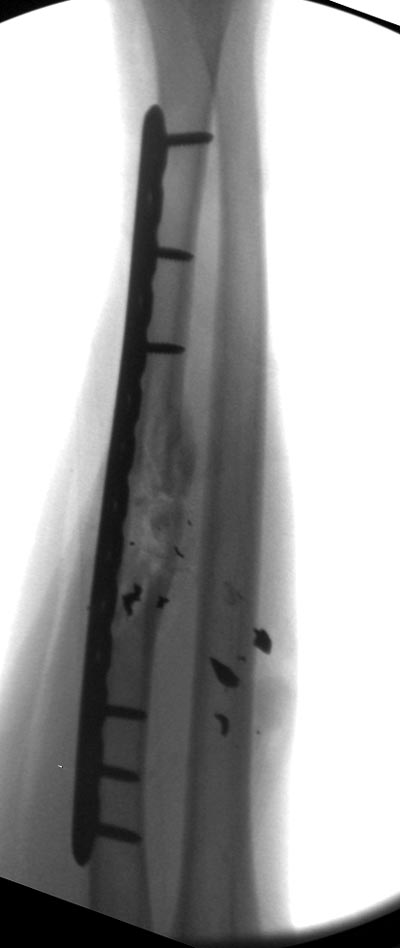

Здесь примеры: двоюродные братья с ранением предплечья, у одного локтевая, а у второго лучевая. В следующее утро локтевая фиксирована без обнажения фокуса травмы из небольших доступов, а второй из обычного волярного доступа. А клинический снимок из прошлых операций...